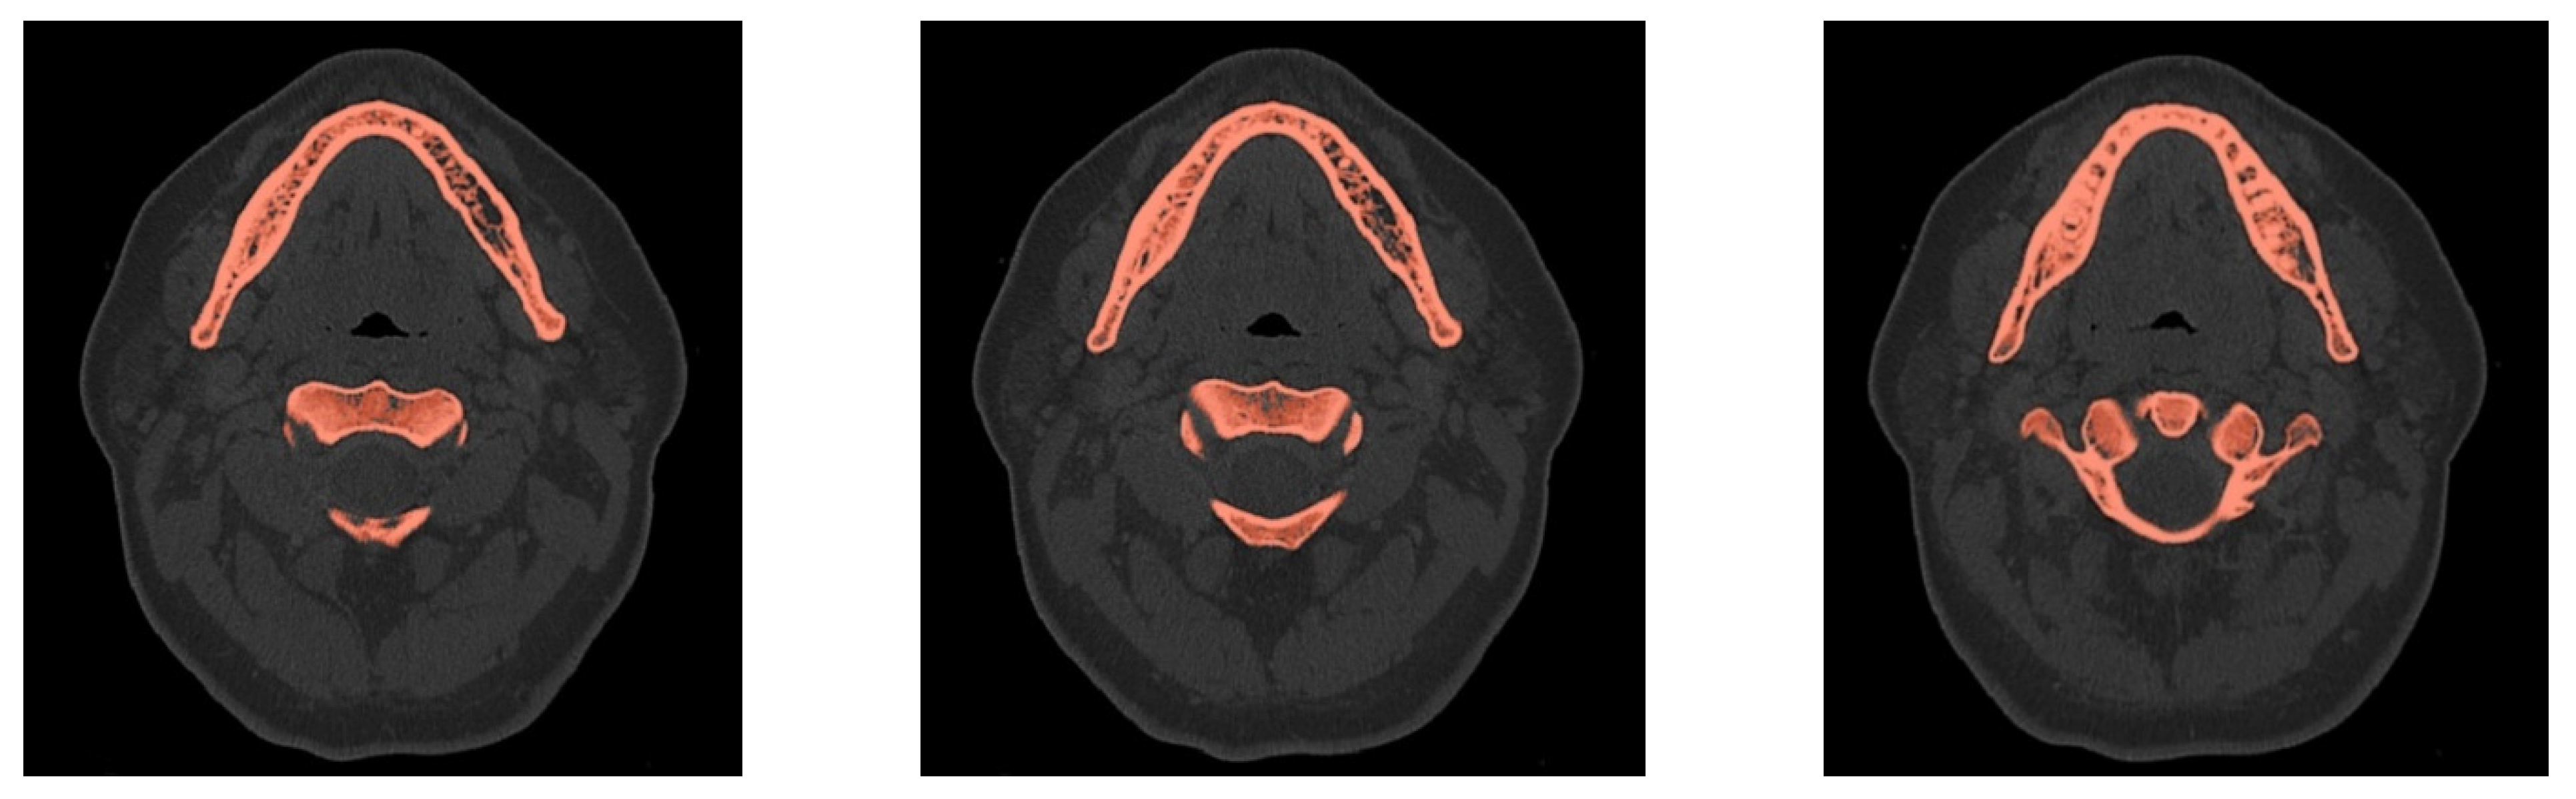

- Creation of an accurate model of the mandible together with the temporomandibular joint. The main assumption was to create a model that could be used for numerical analyses of various clinical cases, allowing the simulation of the work of fixing elements, assessment of the strength and durability of the fixation, and at the same time, without unnecessary simplifications, reflect real human anatomy. The input data were DICOM images obtained from medical imaging using computed tomography. Obtaining three-dimensional models of individual anatomical structures required the segmentation of tomographic images and then edition of the generated surface objects. Reverse engineering software for free modeling and a CAD program for parametric modeling were used.

2.2. Generation of a Three-Dimensional Model of Selected Anatomical Structures